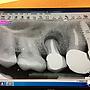

[請益] 四顆門牙做單顆牙套還是牙橋?(有圖慎入)

[ teeth_salon ]15 留言, 推噓總分: +2

作者: sihyu - 發表於 2017/11/13 17:43(8年前)

4Fdontlearn: 我偏好4顆單顆牙套, 較好清潔11/15 00:53

6Fdontlearn: 要看殘留牙齒的量,一般不會很容易就掉下來11/15 13:48

14Fdontlearn: 這就看你決定了吧, 一顆一顆做衛生比較好維持, 牙橋11/18 00:50

15Fdontlearn: 比較不容易斷,各有優缺11/18 00:50